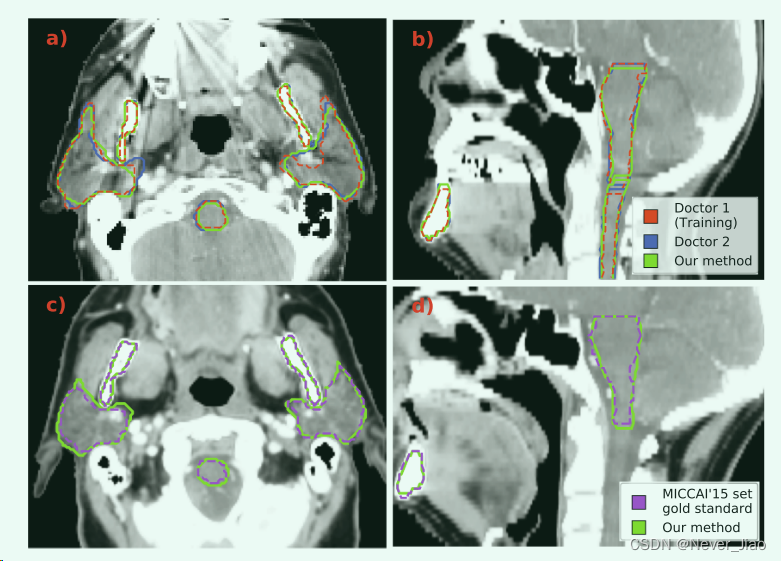

在图 4 中,我们说明了由我们提出的方法产生的示例分割。图 4a 和 4b 显示了来自我们原始数据集的患者的 2D 轴向和矢状切片。图 4c 和 4d 是用于外部验证的 MICCAI’15 集中患者的示例。

Fig.4 我们的 CNN 模型生成的示例分割(绿色)。在第一行 a) 和 b) 中,我们显示了来自我们用于模型开发的数据集的患者的 2D 轴向和矢状视图。该数据集包含由两位医生生成的分割,显示为红色和蓝色。在底行 c) 和 d) 中,我们展示了来自 MICCAI’15 组的患者的轴向和矢状 2D 切片。该集合的黄金标准分割以紫色显示。